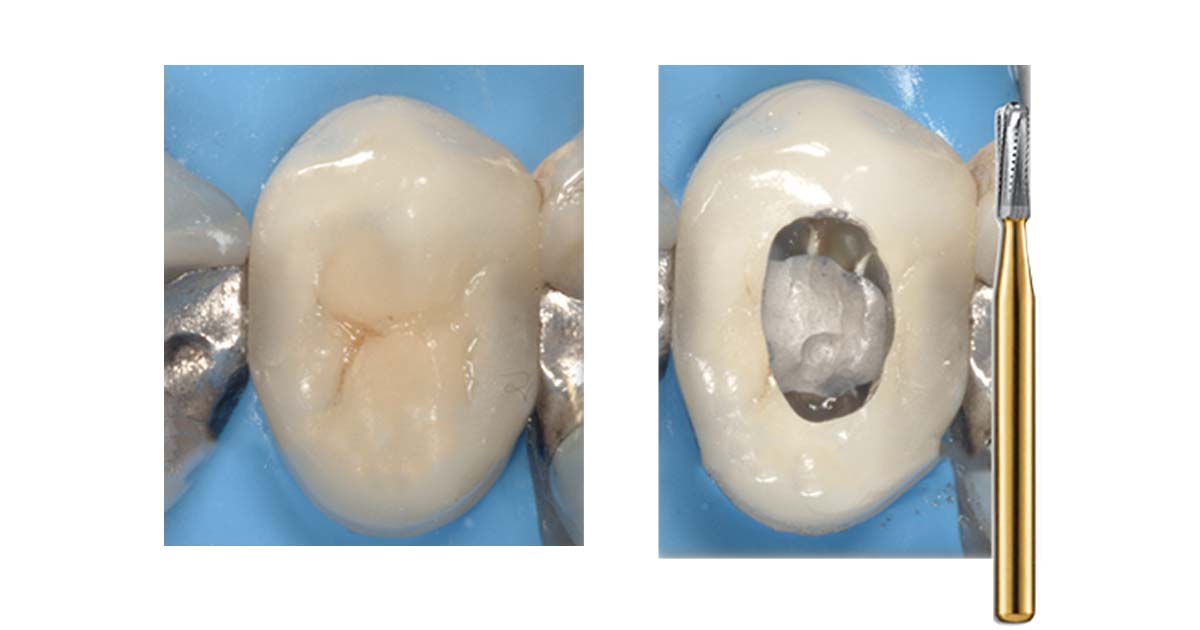

3. Access opening through full-coverage restoration:

When a tooth requiring endodontic treatment already has an existing crown with a good marginal seal, crown removal may not be necessary. However, maintaining proper bur orientation and parallelism with the tooth's long axis during access opening can be challenging. Failure to do so may lead to incomplete caries removal, perforations, or inadequate cleaning and shaping, ultimately causing endodontic failures.